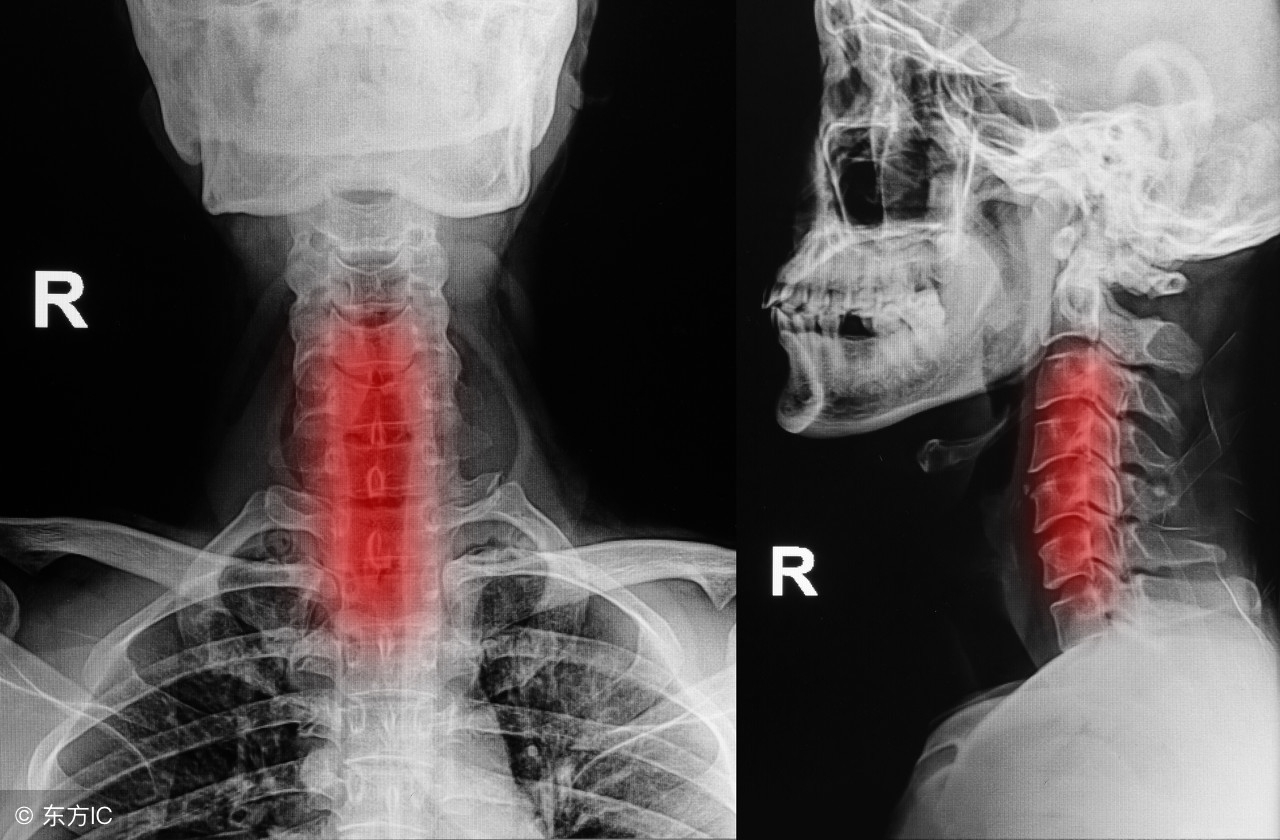

骨刺的好发部位有跟骨,腰椎,颈椎,膝关节等,从我们的生活方式不难看出,为什么这些部分好发骨刺,因为长时间的久坐少动,是脊椎压力增加退变加快,长时间的跑跳,过度运动容易造成膝盖和跟骨的骨刺。